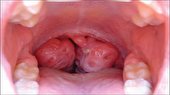

آناناس میان‌وعده‌ای با‌طراوت و سرشار از ویتامین‌های CوB۶ است که آن را به یک خوراکی مفید رژیمی در میان سایر خوراکی‌ها تبدیل کرده. علاوه بر ویتامین‌ها و مواد معدنی، این میوه تابستانی آنزیم قدرتمندی دارد که به عنوان نرم‌کننده گوشت استفاده می‌شود.